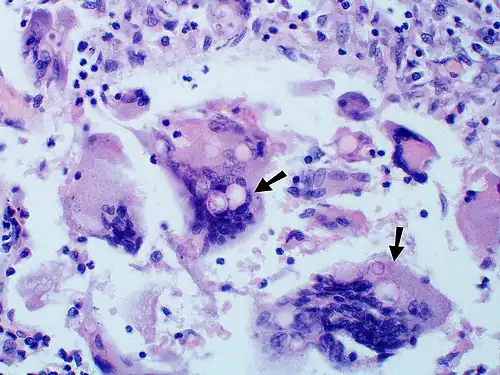

Granuloma with early suppuration. The fungal organisms are difficult to recognize at this low magnification. -

Large yeast-like fungi seen within giant cells at arrows. -

Large yeast-like fungi seen within giant cells at arrows. Budding yeasts in the cytoplasm of giant cells at the arrows. Broad-based budding and double-contoured cell walls are seen in the giant cell in the center are characteristic of Blastomyces dermatitidis. -